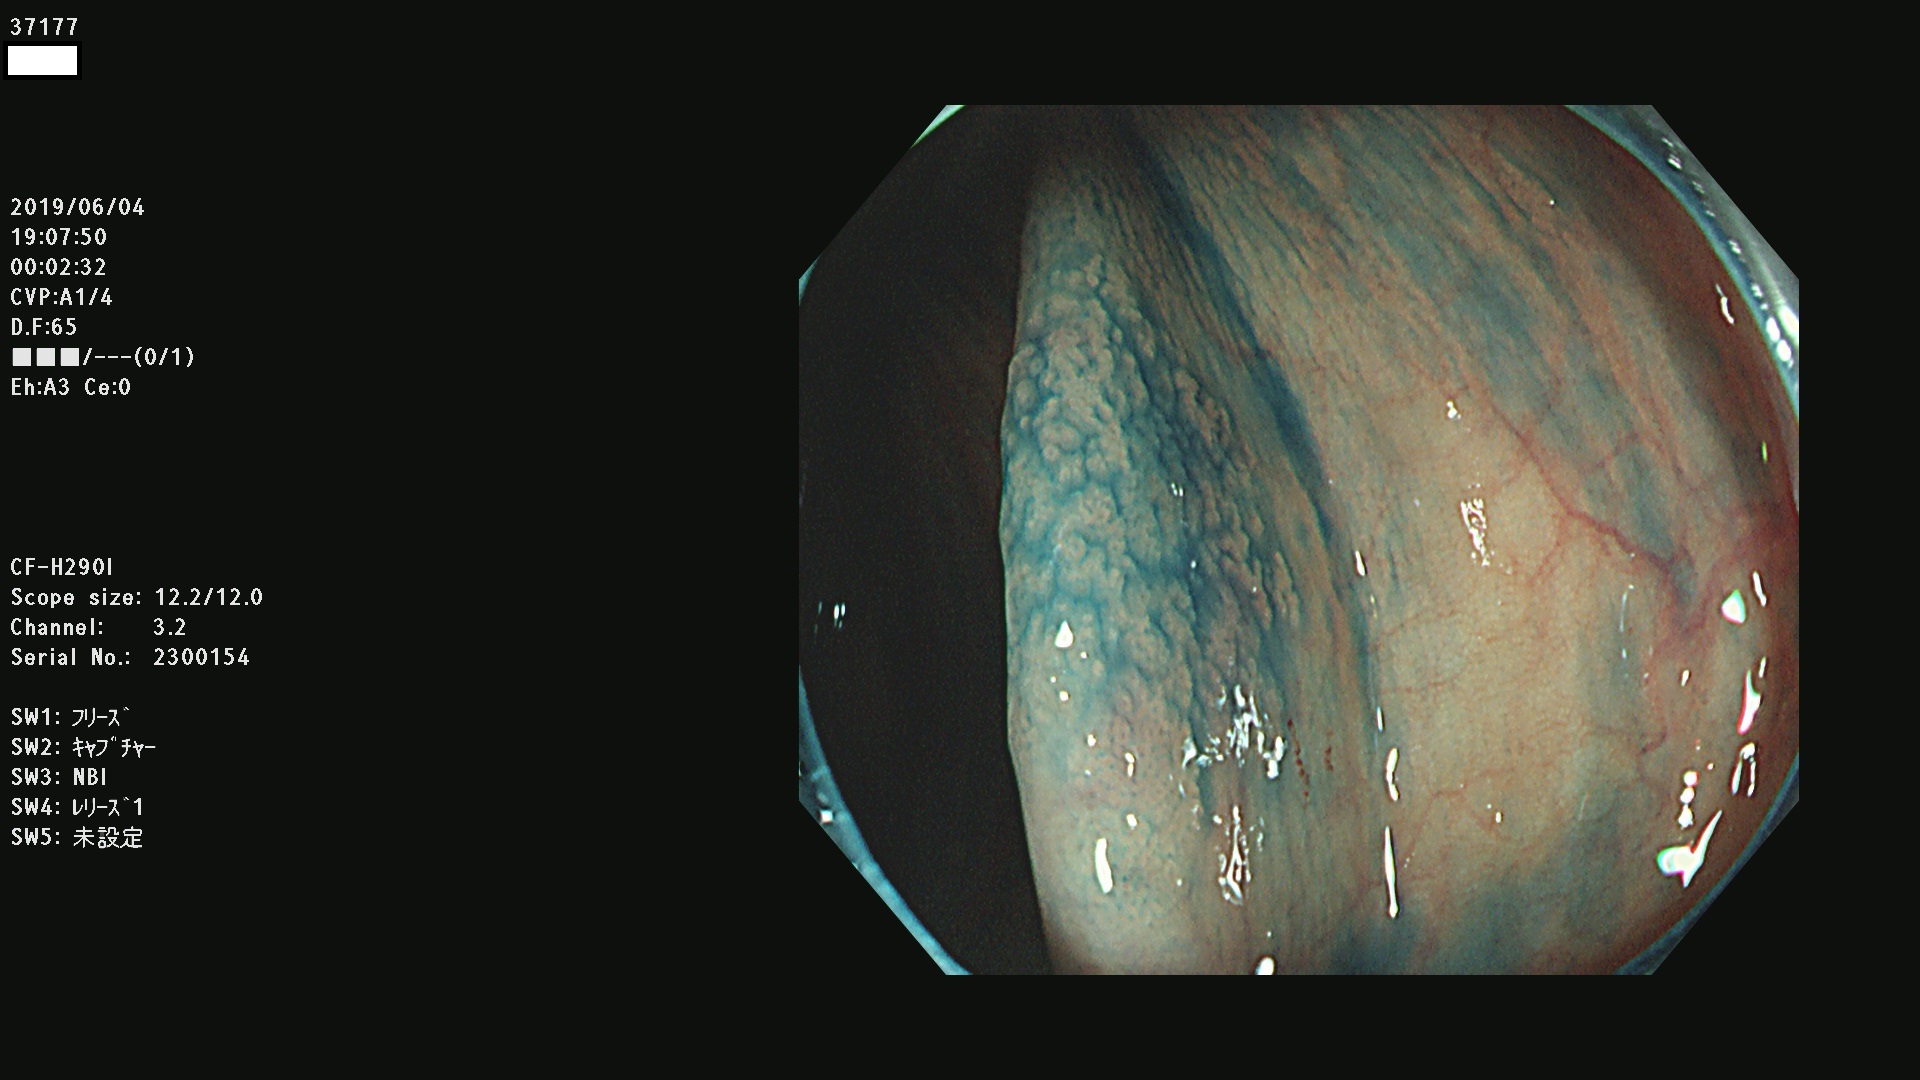

37100 37101 37102 37104 37106 37108 37110 37111 37112 37113 37115 37118(SSAPのみ) 37120 37122 37123 37124 37127(SSAPのみ) 37128(SSAPのみ) 37131 37132 37133 37134 37135 37139 37141 37142 37143 37144(SSAPのみ) 37145 37147(SSAPのみ) 37148 37149 37150 37153 37154 37157 37159 37161 37162 37163 37164 37165 37166 37167 37168 37169 37170 37171 37172 37173 37175(SSAPのみ) 37176 37177 37178 37180(SSAPのみ) 37181 37184 37185 37186 37187 37188 37189 37190 37192 37194 37197 37198

発見困難で危険性の高い平坦型病変(上記100名より抽出)